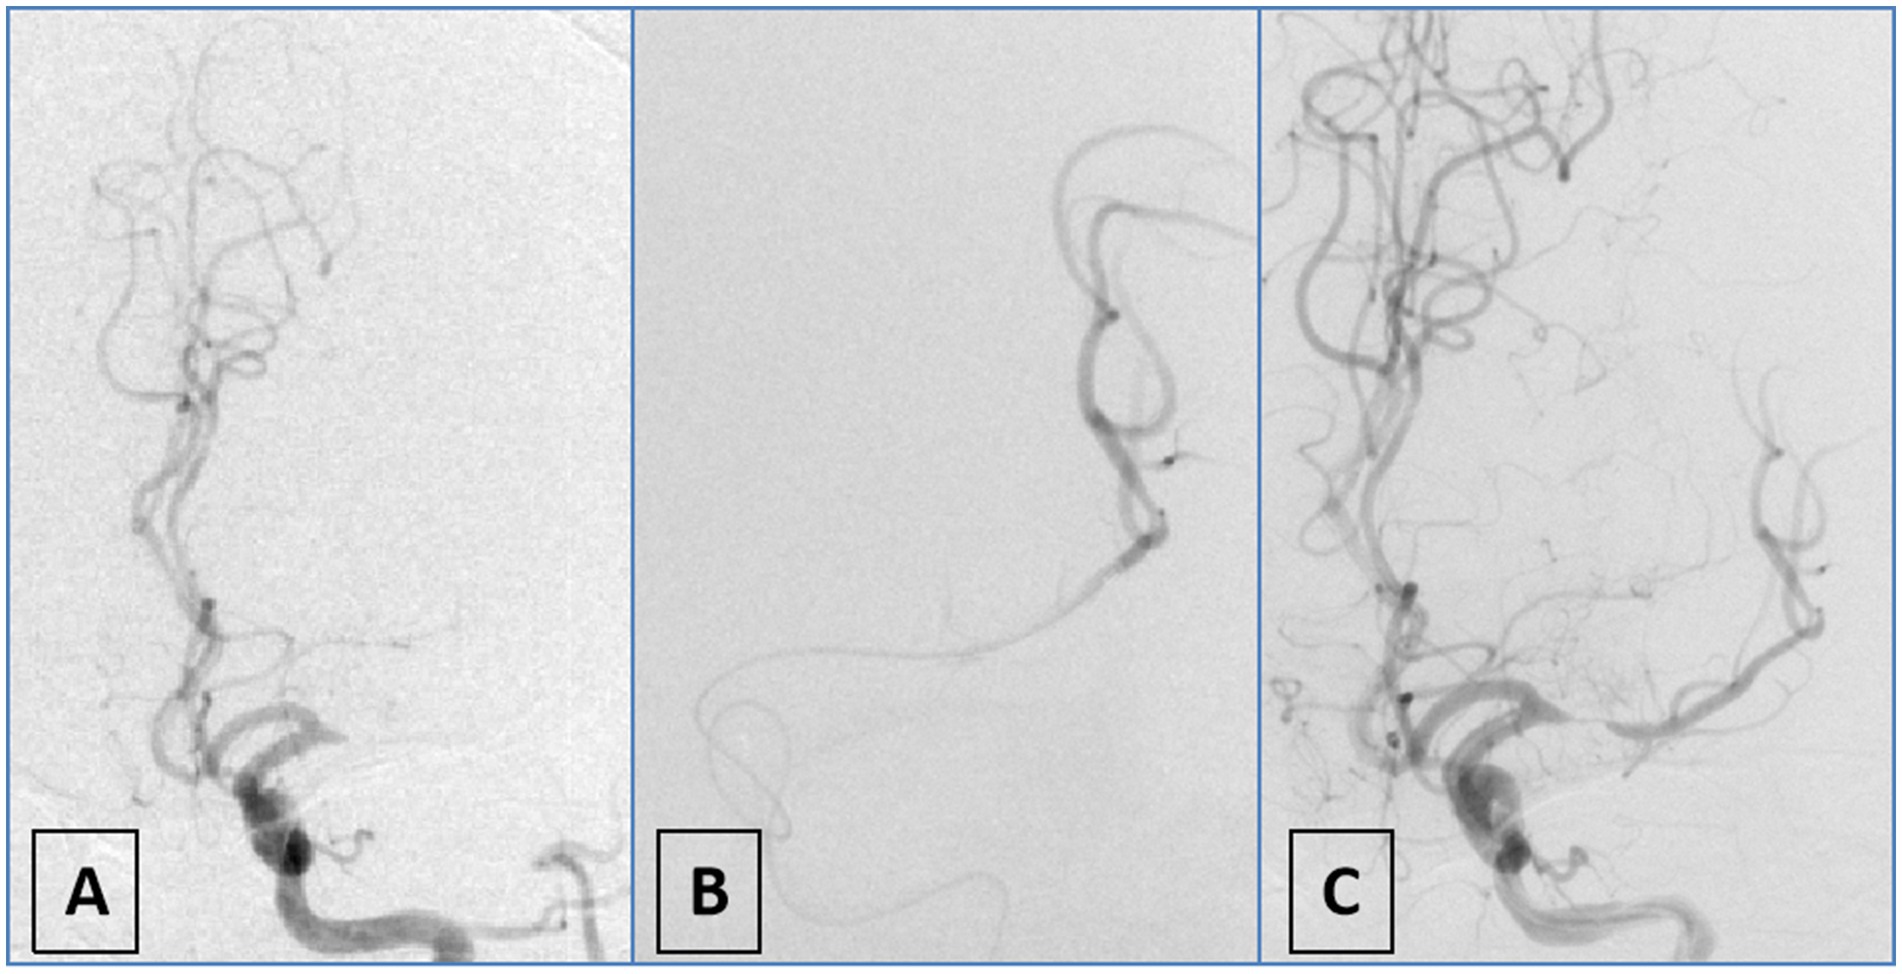

Patients were included if they were ≥ 18 years of age, had no evidence of intracranial hemorrhage on baseline non-contrast CT or MRI, and had an intracranial LVO confirmed by CTA, MRA, or DSA. Occlusions of the vertebral artery V4 segment were included only in the presence of contralateral vertebral artery hypoplasia or occlusion. The underlying etiology of ICAD-LVO was determined using a positive microcatheter first-pass effect (15) (Figure 1). Additional inclusion criteria consisted of a baseline National Institutes of Health Stroke Scale [NIHSS] score ≥6, indicating moderate to severe deficits, and an onset-to-puncture time within 24 h. Key exclusion criteria covered procedural termination before implementation of the initial approach, pre-stroke functional dependence (defined as mRS > 1), and the presence of ≥70% stenosis or occlusion proximal to the occluded vessel suggestive of an artery-to-artery embolism mechanism. We also excluded patients with refractory hypertension (>185/110 mmHg despite medication), severe dysglycemia (blood glucose <2.7 or >22.2 mmol/L), coagulopathy (platelet count <40 × 109/L, aPTT >50 s, or INR > 3), and those with incomplete clinical or angiographic data. These criteria were applied to minimize confounding related to comorbidities, technical variability, and data reliability issues. The final analysis included 161 patients with ICAD-LVO, who were classified into two groups according to the initial endovascular strategy: the AS group and the MT group (Figure 2).

Figure 1. Schematic diagram of first-pass effect positivity. (A) DSA angiography demonstrates occlusion of the M1 segment of the left middle cerebral artery; (B) the microwire and microcatheter traverse the lesion to reach the distal vasculature, confirming intraluminal positioning; (C) repeat angiography after partial withdrawal of the microcatheter reveals severe stenosis in the M1 segment of the left middle cerebral artery.

Diagnosis of underlying ICAD-LVO

Diagnosis of underlying ICAD-LVO in this study was primarily determined through preprocedural clinical data, preprocedural CTA, and intraprocedural DSA imaging. First, suspicion for ICAD-LVO arose if patients had preexisting atherosclerotic risk factors (hypertension; diabetes; smoking) (16, 17) or exhibited trunk occlusion rather than branch occlusion (18). Operators subsequently verified the diagnosis intraprocedurally using the microcatheter first-pass effect (15). To evaluate this effect, the microcatheter was advanced with the microguidewire through the occlusion into the distal patent segment and then withdrawn to a position proximal to the occlusion while the microguidewire remained in place, after which angiography was performed via an intermediate catheter. A positive result was defined as the angiographic demonstration of both transient antegrade flow and an underlying severe stenosis at the occlusion site, a finding indicative of an underlying ICAD-LVO. The absence of flow (persistent occlusion) was considered a negative result, suggestive of an embolic etiology (Figure 1). Diagnosis was made intraoperatively by the operator and prospectively recorded in the database. Subsequently, another neurointerventionalist reviewed the diagnosis. Discrepancies were resolved through unanimous consensus.